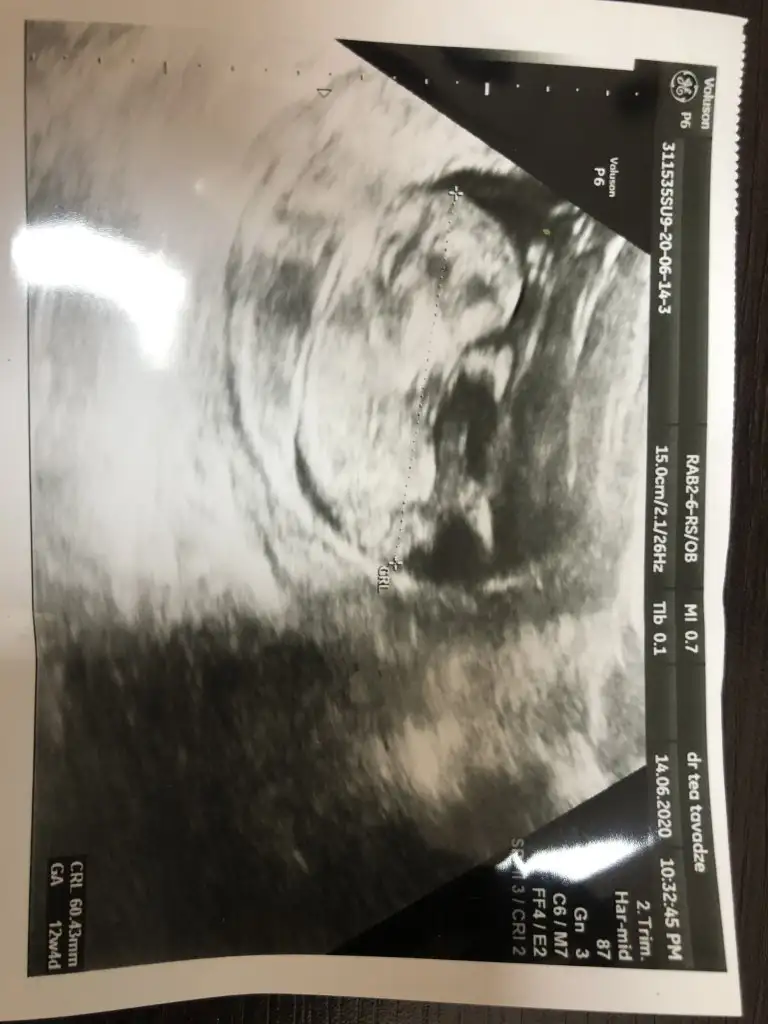

Kaç haftalık net değil cnm puslu olmuş resimIkra meyra Eki Görüntüle 2649669 Eki Görüntüle 2649670 merhaba bi arkadasimin resimlerini aticam tahmin edermisinkz.

11 hafta 4 gunluk dedi videodan alinti yapmis elinde baska resim yok coknmerak ediyo 2 kizi var bu 3. Degisik olsun istiyoKaç haftalık net değil cnm puslu olmuş resim

Erkek gibi ama emin olamadım o neden usg istedim 13 hafta olursa paylaşın emin olmak istiyorum çünki net değil11 hafta 4 gunluk dedi videodan alinti yapmis elinde baska resim yok coknmerak ediyo 2 kizi var bu 3. Degisik olsun istiyo

Hiç net değil usg siyah usg olsa daha net olurdu 11 12 13 hafta usg olmalı

12 haftalik burda renksizi yakalayamadim o yuzdenHiç net değil usg siyah usg olsa daha net olurdu 11 12 13 hafta usg olmalı